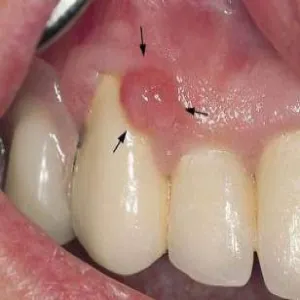

Nadziąślak

Nadziąślak, epulis